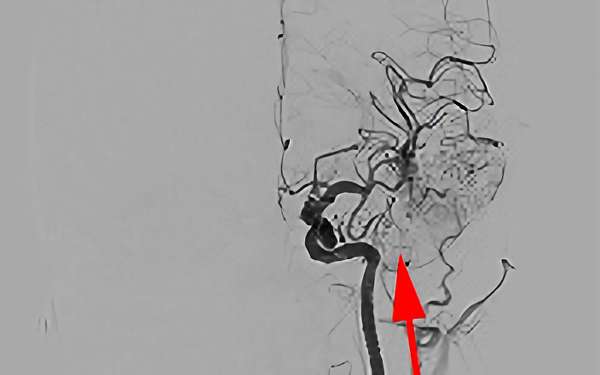

'25年9月

脳動静脈奇形

20代

愛知県の病院

No.1576 手術前

No.1576 手術中

No.1576 手術後